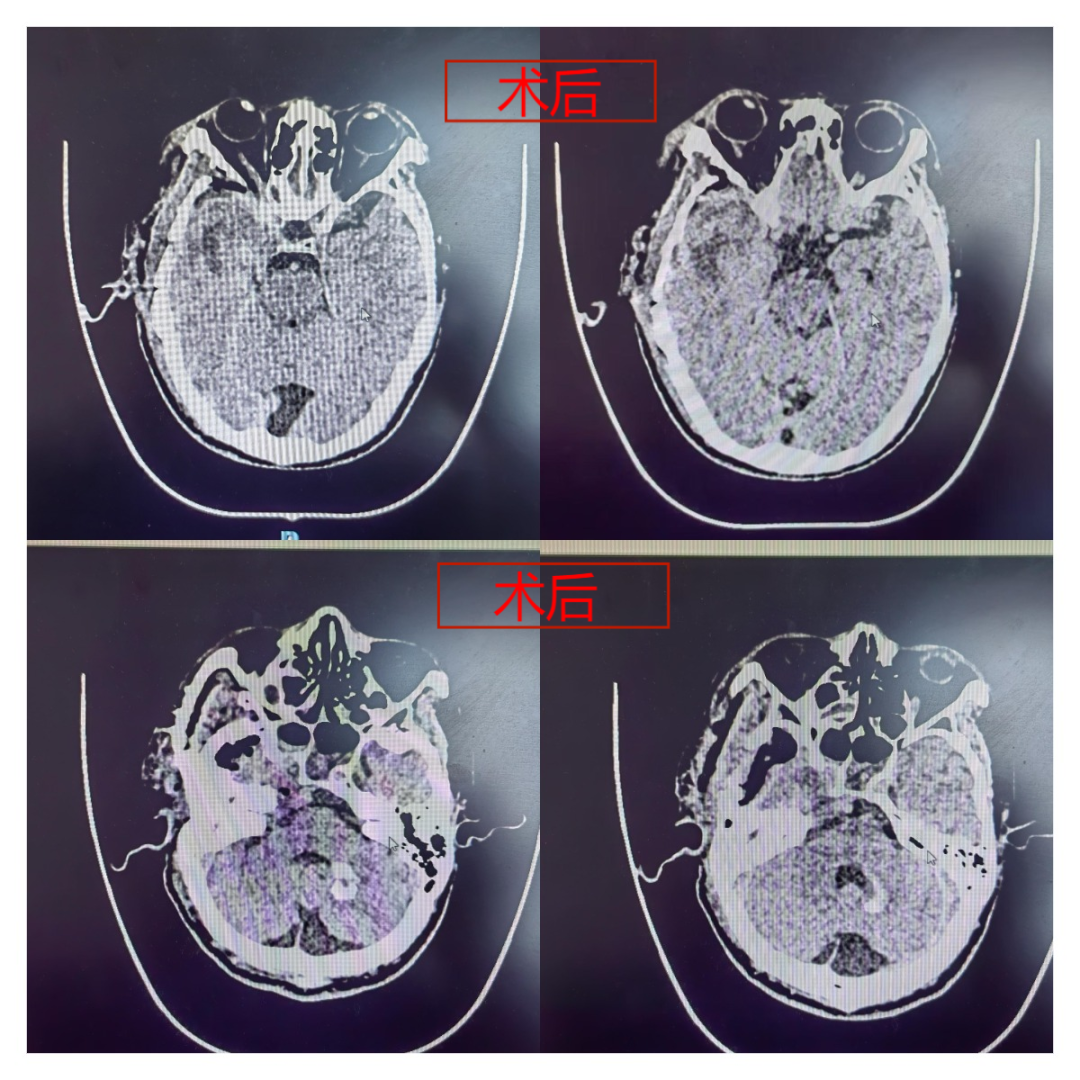

尽管困难重重,但郭清保主任及其团队没有退缩。手术过程中,当面对颈内动脉及脑干附着面这一关键且危险的部位时,郭主任凭借着丰富的经验和精湛的技术,谨慎地剥离肿物,同时密切关注着患者的生命体征变化。经过紧张而细致的操作,手术顺利完成。

令人欣喜的是,薛大爷术后正常苏醒,神经功能完好无损地保留了下来。一周后,薛大爷已经能够下地行走,恢复状况良好。郭清保主任再三叮嘱薛大爷要定期复查,以确保身体持续康复。